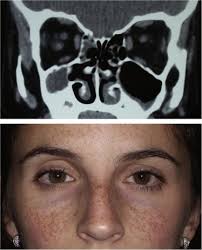

A Clinical Photograph Of A 38 Year Old Female With Silent Sinus Download Scientific Diagram